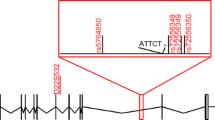

All of the patients recruited in this study had an insertion ranging from 2.6 to 3.7 kb in length. Direct sequencing confirmed that the insertion contained (TGGAA)n stretch in all of the patients. The average length of the insertions was approximately 3,130 bp (SD, 199 bp) (n = 94). The correlation between the size of the insertion and the age at onset is shown in Fig. 1. The length of the insertion was inversely correlated with the age at onset (n = 89). We observed six intergenerational transmission of a disease-causing allele in five families in our cohort. There was no conspicuous expansion of the insertion size.

Correlation between the insertion size and age at onset (n = 89). Representative PCR screening for the SCA31 insertion (a). Agarose gel electrophoresis of PCR products before and after HaeIII digestion is shown. M GeneRulerTM 1-kb Ladder (Fermentas Life Sciences, Burlington, Canada). The size of the insertion is inversely correlated with the age at onset (b). For 5 of 94 patients, age at onset could not be clearly defined by medical interview